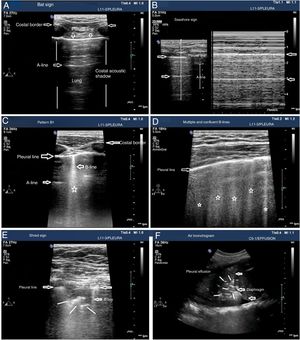

The patterns of airing of each pulmonar region are (Fig. 2):

- •

Pattern A: typical pattern of normal airing. Pleural line with preserved sliding, presence of well spaced A-lines and ≤ 2 B-lines (Fig. 2A and figure B).

Pattern B1: presence of more than 2 well spaced, diffuse B-lines in different thoracic regions called septal rockets (Fig. 2C).

Pattern B2: confluent B-lines separated between them by ≤ 3mm (ground-glass rockets) due to a more severe loss of aired lung (Fig. 2D).

Pattern C: lung consolidation suggestive of significant loss of airing of the lung due to the accumulation of fluid and/or cells in the alveoli. The consolidation can be found anywhere in the hemithorax but applying the transducer to the PLAS point detects 95% of the cases (Fig. 2E and figure F).

Patterns of airing of the pulmonary region. A) Typical pattern of normal airing (profile A in the BLUE protocol) showing 2D imaging. B) Pattern A on M-mode. C. Pattern B1. D) Pattern B2. E) Pulmonary consolidation (profile C in the BLUE protocol) showing shred sign. F) Air bronchogram. A, B, C, D, and E: linear probe study; F, convex probe.

Patterns A, B1, and B2 include the presence of lung sliding (Appendix B annex 3 of the DSD).